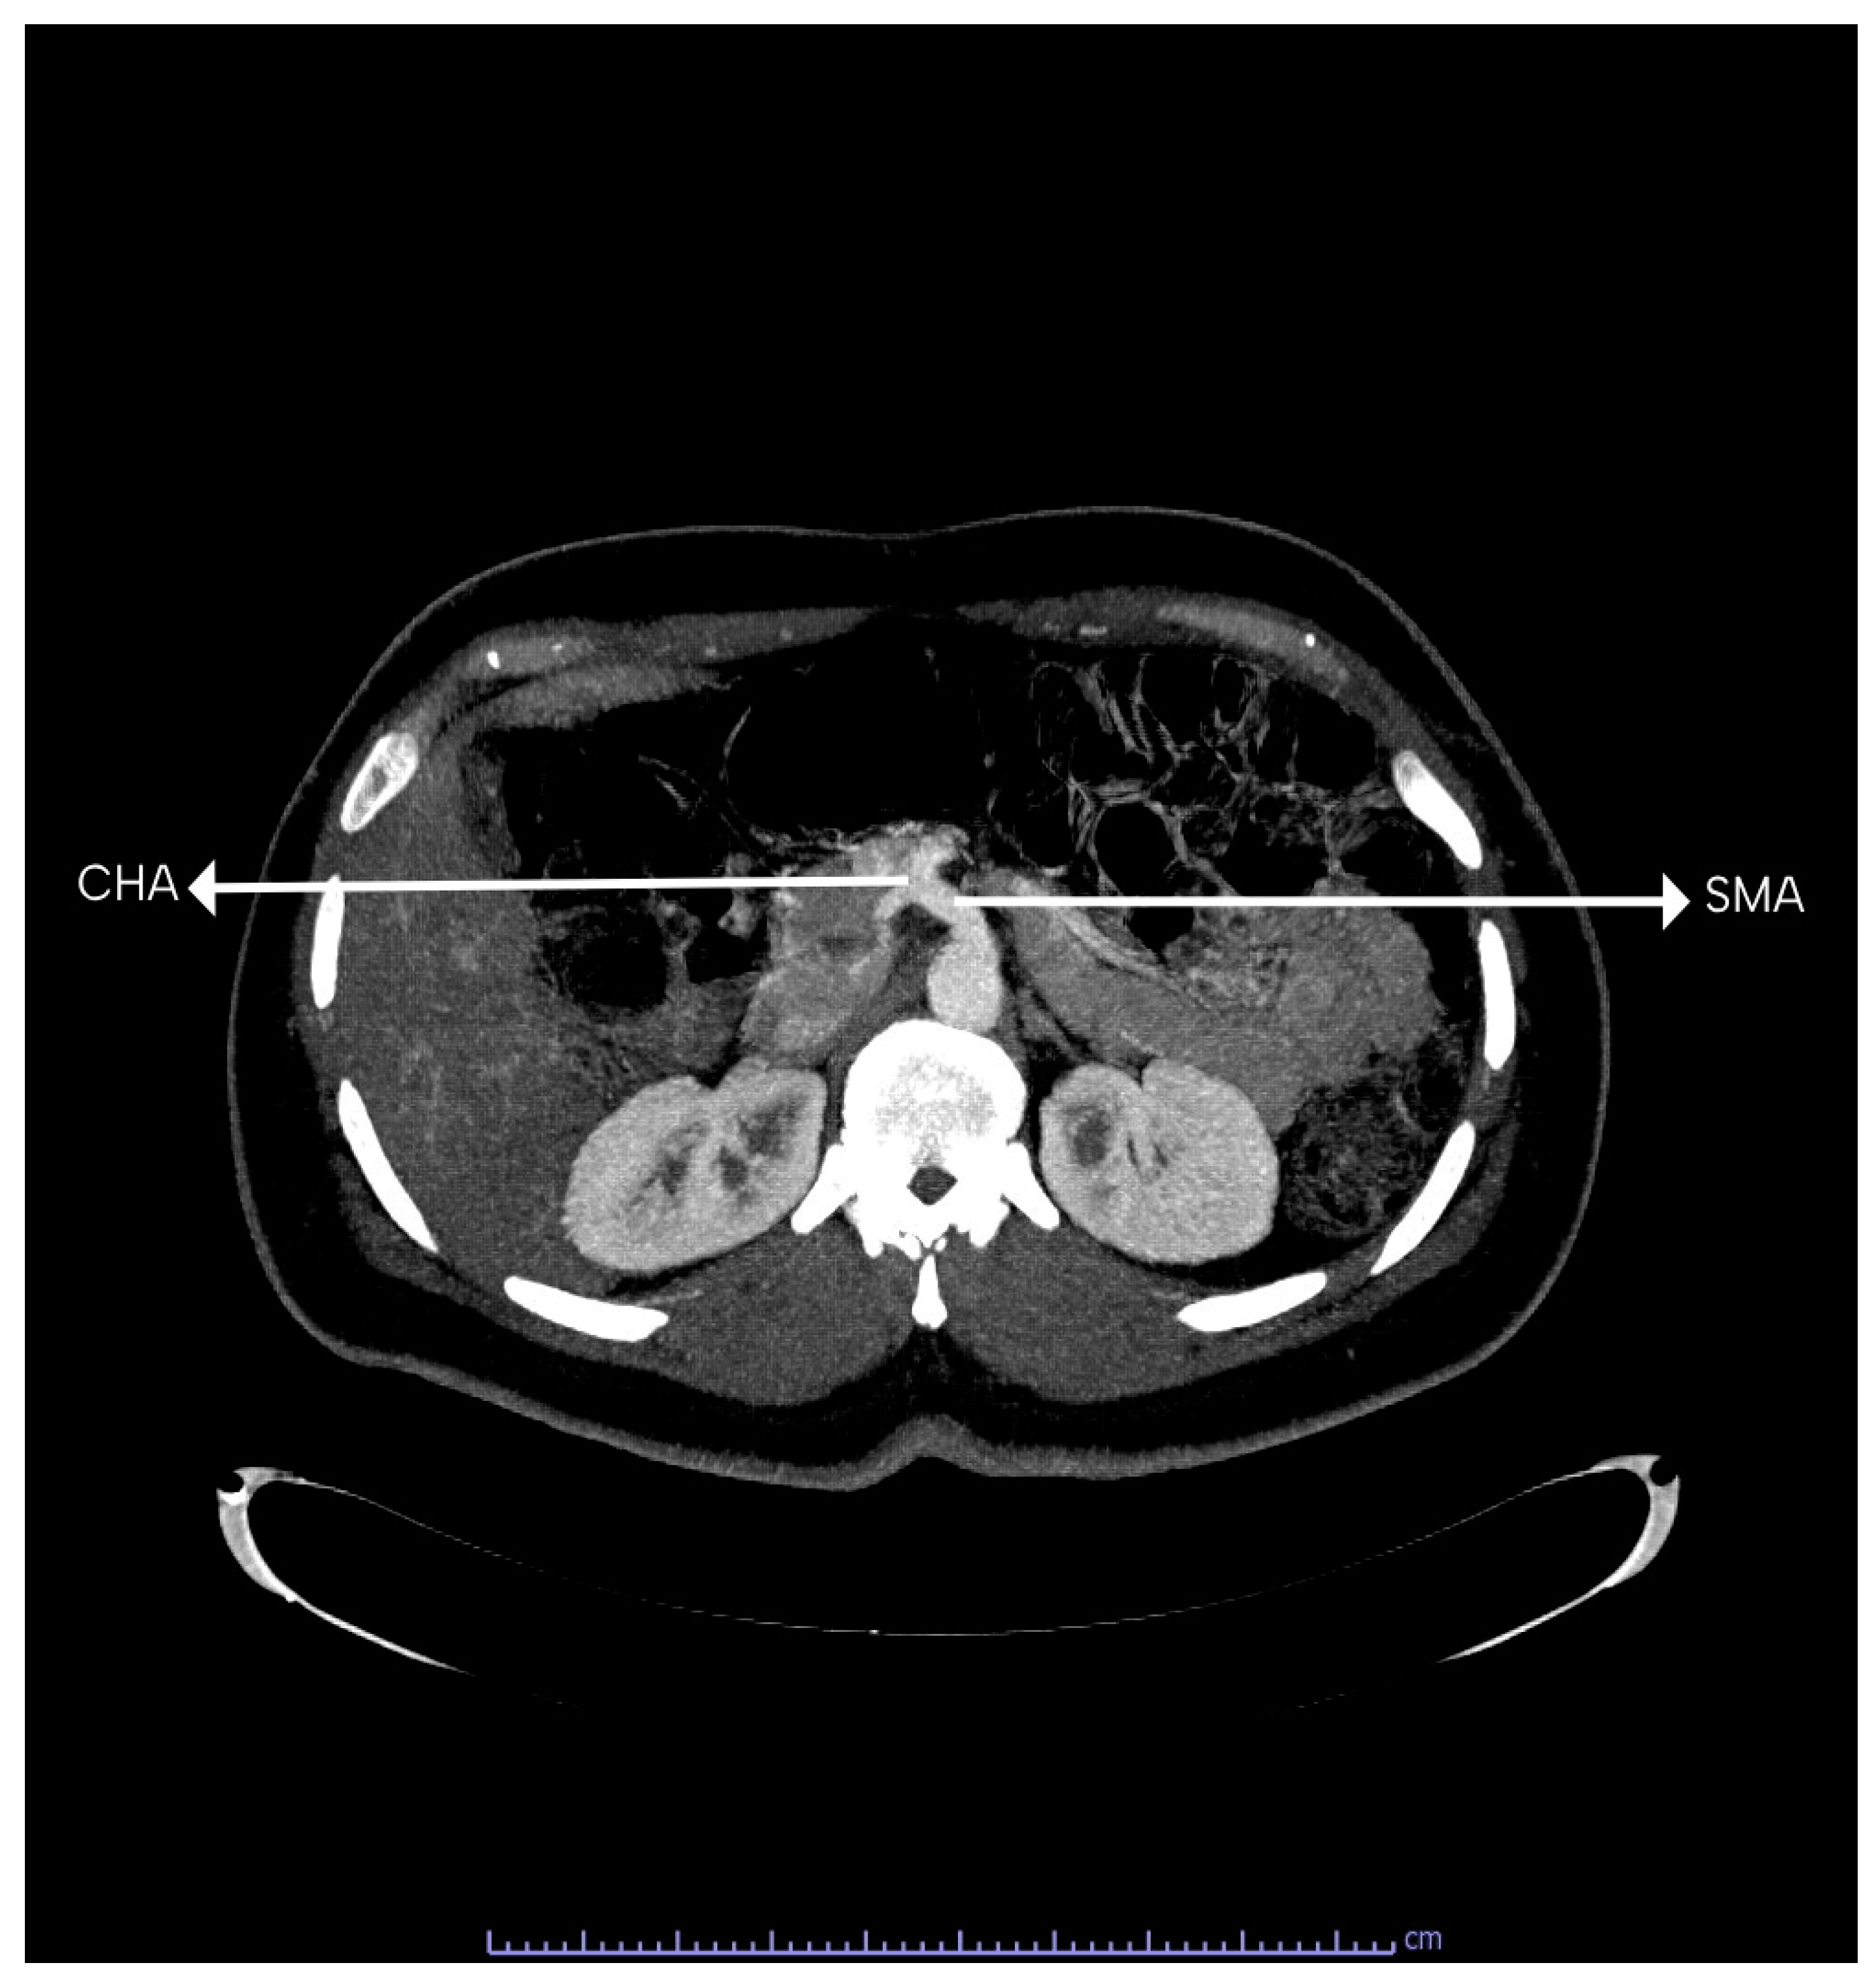

The CT normally trifurcates into the left gastric, splenic, and common hepatic arteries. Figure 5 shows the 3D construction of the normal branching of the CT. The CT showed classical trifurcation in 112 (96.60%) patients, where it divided into the splenic artery, left gastric artery, and the common hepatic artery. In the other four patients, bifurcation of the CT was observed. In two (1.70%) out of the four patients (one male and one female), the CT gave rise to the splenic and left gastric artery (gastrosplenic trunk; Uflacker’s type V), while the common hepatic artery took origin from the superior mesenteric artery. Figure 6 shows a common hepatic artery originating from the superior mesenteric artery. In the other two patients (1.70%) (one male and one female), the CT gave rise to the splenic and common hepatic artery (hepatosplenic trunk; Uflacker’s type II), while the left gastric artery arose as a direct branch from the abdominal aorta. Figure 7 shows the left gastric originating from the abdominal aorta, while the CT bifurcates into the SA and common hepatic artery.

Figure 6. A computed tomography scan showing common hepatic artery (CHA) taking origin from the superior mesenteric artery (SMA).